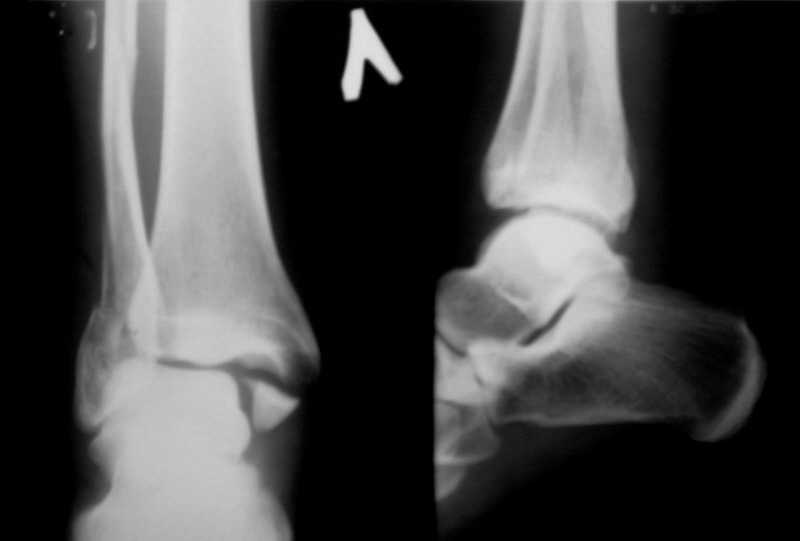

Вот рентгенконтроль на 7-е сутки после репозиции.

Стандартными снимками считается прямая, боковая и мортиз!!!, а так трудно гадать, насколько потеря длины малоберцовой. На боковом снимке не сопоставленный перелом медиальной лодыжки и перелом заднего края без смещения.

In this case we say about three malleolar fracture of ankle.Moreover lateral malleolus have external rotation displacement.Becouse this great suprise to me question - what kind of treatment.Of course open reduction with internal

Ув. коллеги. Мы считаем, что синтезировать необходимо медиальную лодыжку, она ротирована. Малоберцовую кость лучше не трогать. Довольно травматично будет, фрагменты неплохо стоят. И то, оперировать медиальную лодыжку где-то в трехнедельном сроке, чтобы малоберцовую кость не развалить. Мнений много, мы благодарны за участие.

Очень жаль, что Вы так считаете и не прислушались к мнениям уважаемых коллег. Проблема этого голеностопного сустава не в "висячей" внутренней лодыжки, а ротированной и, возможно, укороченной малоберцовой кости. На снимках подвывиха как-буд-то бы нет, но таран ротирован и это в дольнейшем будет причиной раннего артроза.